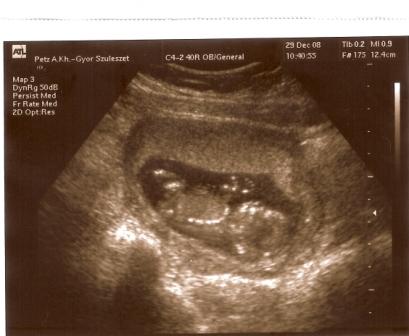

Ma vagyunk 10 hetesek, voltam 29-én ultrahangon, dobogott a szívecskénk, kaptunk képet is. 2,5 cm-es volt a picur. Január 21-én megyek integrált tesztre a Mátyásföld Klinikára. Volt már ott valaki? Akkor leszek 12 + 5 napos. Aki ilyen integrált teszten átesett, mesélne róla?

Küldöm a fotót, remélem látjátok rajta a lényeget, meg is fordítottam!

Baba 9+3 nap